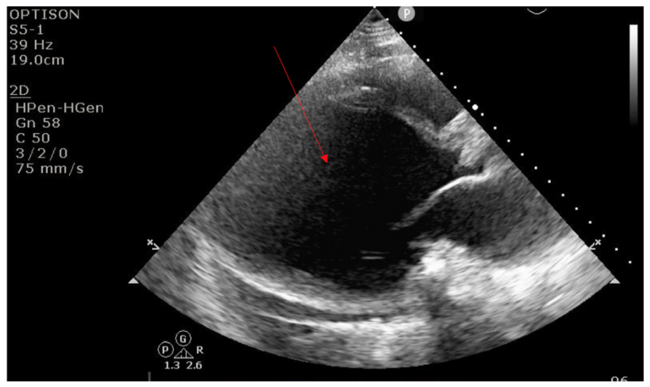

Left ventricular (LV) unloading has been associated with improved survival in patients treated with venoarterial extracorporeal membrane oxygenation (VA-ECMO).1 This case visually demonstrates the effect of LV unloading in a 30-year-old male, with a history of coronavirus disease 2019 (COVID-19) myocarditis. The patient developed COVID-19 and subsequently developed nonischemic cardiomyopathy with an LV ejection fraction of 10% to 15% (baseline echo; Figure 1, Video 1). He did poorly in the outpatient setting and was admitted to an outside hospital with heart failure symptoms. He was subsequently transferred to our hospital for escalation of care and consideration of advanced heart failure therapies. Upon arrival to our institution, the patient experienced a cardiac arrest with refractory ventricular fibrillation. Given his young age, VA-ECMO was inserted at bedside. The patient was brought to the cardiac catheterization lab for LV unloading with Impella due to inadequate aortic valve opening and LV smoke. On the following day, the patient had low-flow alarms. Echocardiogram demonstrated complete obliteration of the LV cavity (Figure 2, Video 2). The patient was transfused 2 units of red blood cells and given intravenous fluids with improvement in flow. The case nicely demonstrates the effect of LV unloading in the setting of VA-ECMO.